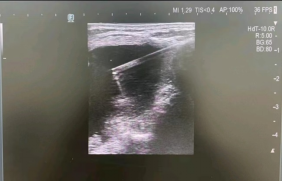

袁医生联合超声科主任邵军

在局麻下为胡奶奶实施了

甲状腺肿块微波消融术

术中按照术前既定的穿刺路线

麻醉针精准定位至结节病灶

3分钟后病灶成功被“热损毁”